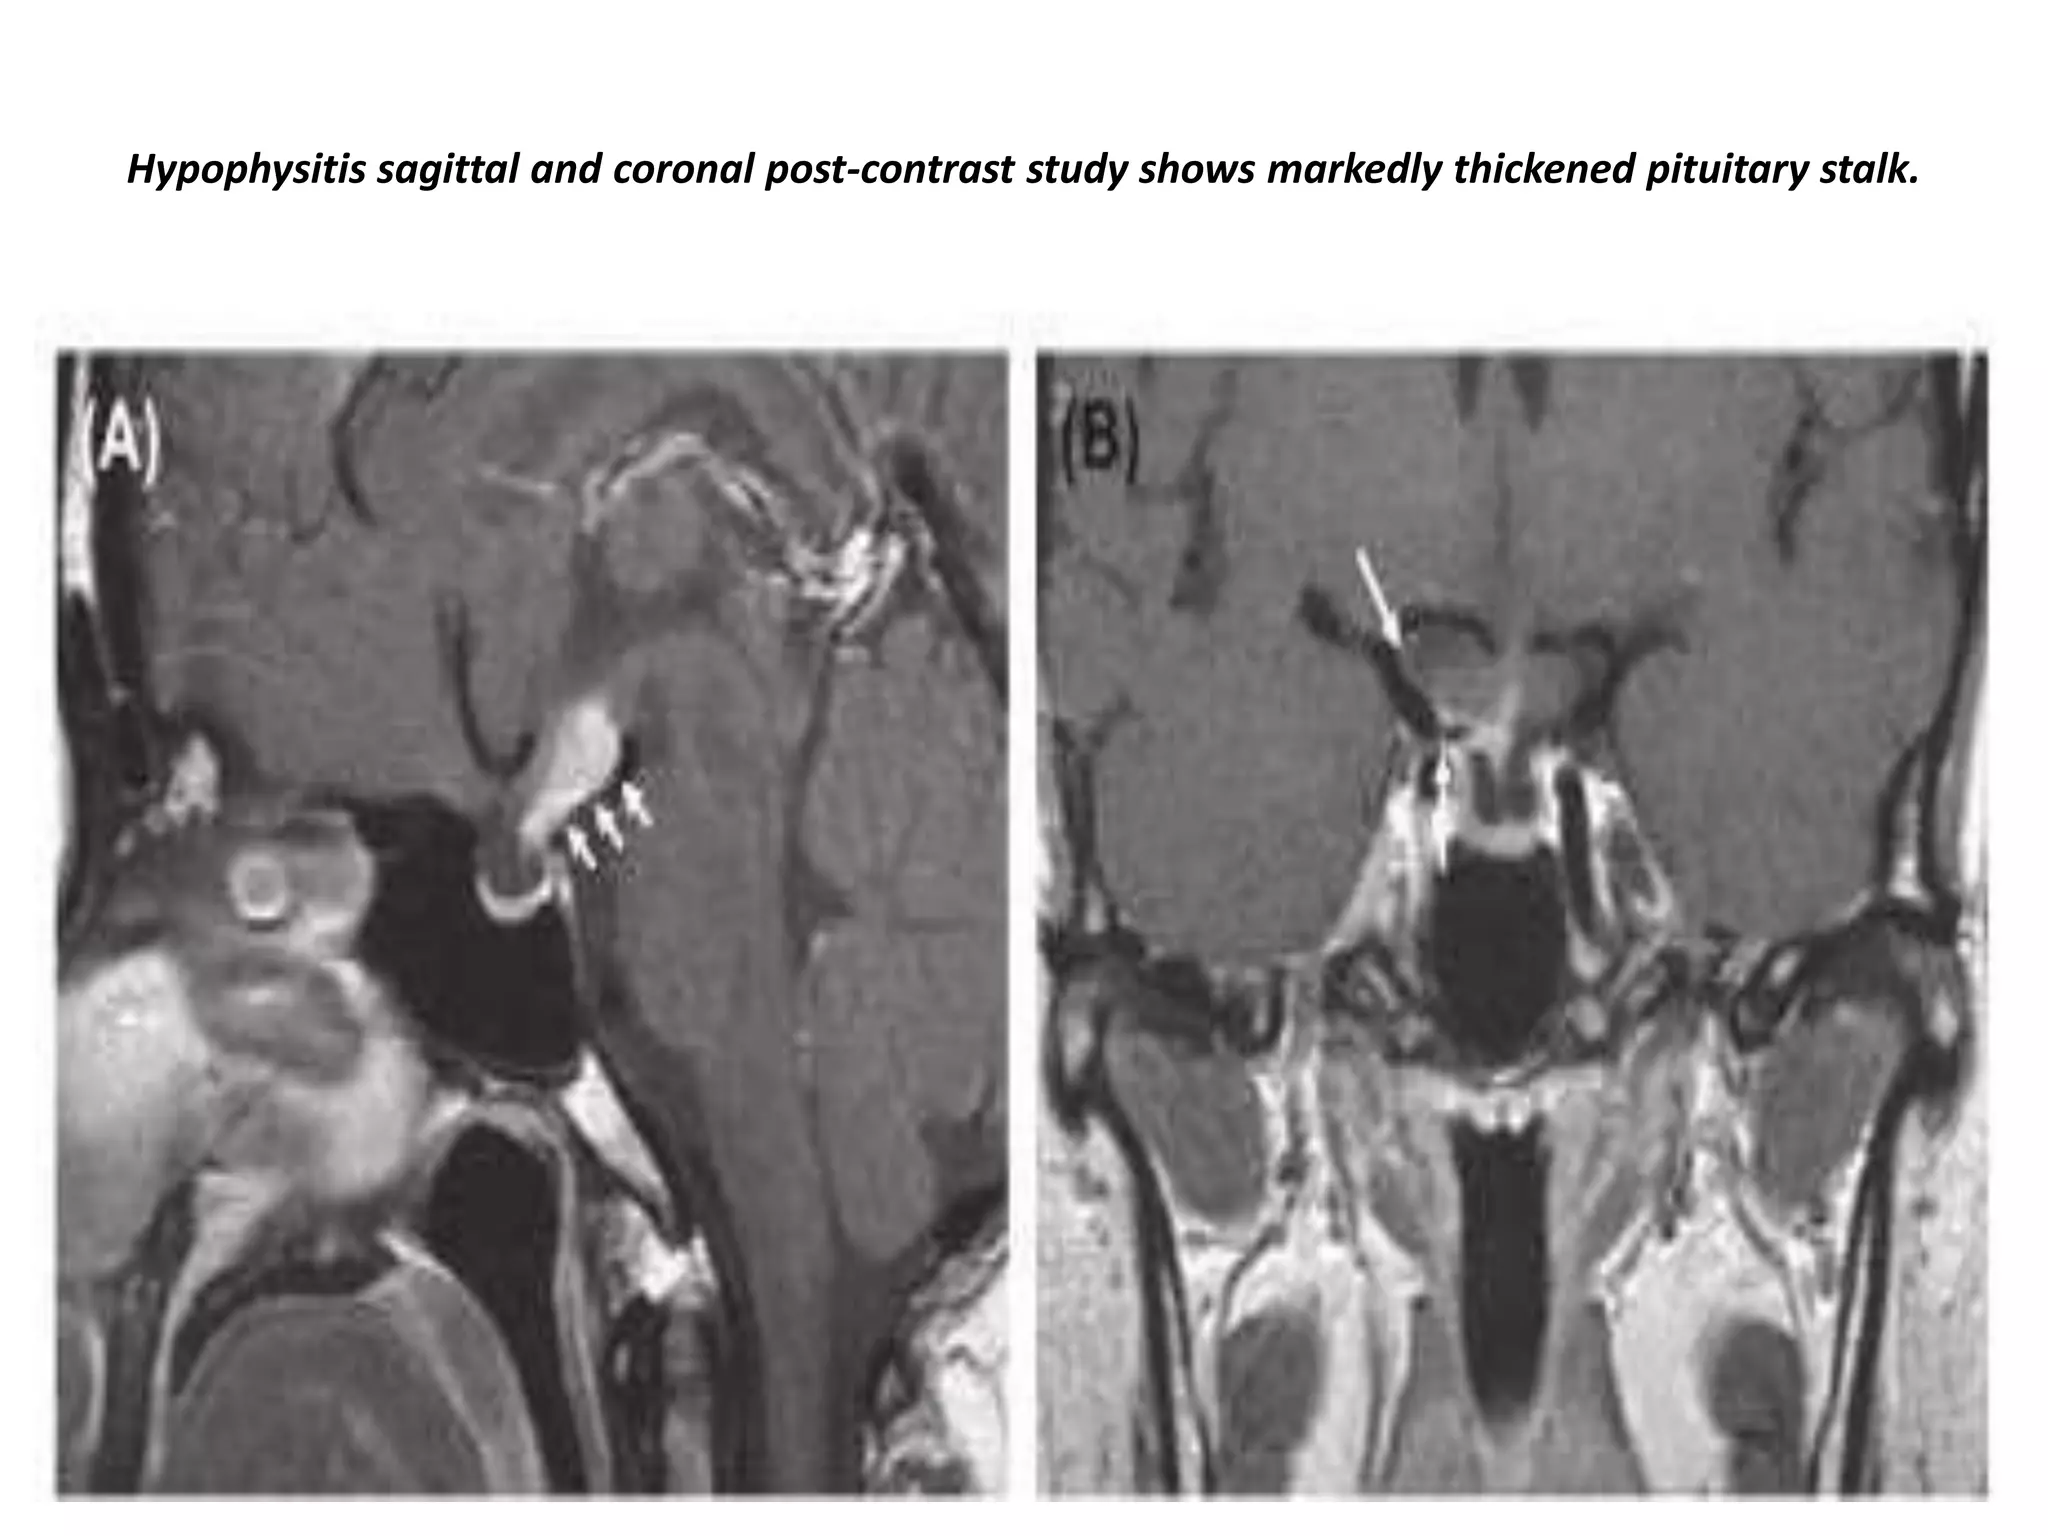

Hypophysitis with thickening of the pituitary stalk in combination with an intense

contrast enhancement (coronal and sagittal imaging).

Hypophysitis sagittal and coronal post-contrast study shows markedly thickened pituitary stalk.